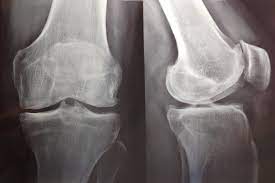

Hay evidencia de certeza alta de que el uso de antidepresivos para la artrosis de rodilla produce una mejoría insignificante desde el punto de vista clínico en el dolor medio y la funcionalidad. Sin embargo, un pequeño número de personas tendrá una mejoría importante del 50% o más en el dolor y la funcionalidad. Este hallazgo fue consistente en todos los ensayos. El dolor en la artrosis se podría deber a diversas causas que difieren entre las personas. Es posible que la causa del dolor que responde a este tratamiento solo esté presente en un pequeño número de personas. Hay evidencia de certeza moderada de que los antidepresivos tienen un pequeño efecto positivo sobre la calidad de vida, con heterogeneidad entre los ensayos. Cochrane Database of Systematic Reviews 21 de octubre de 2022